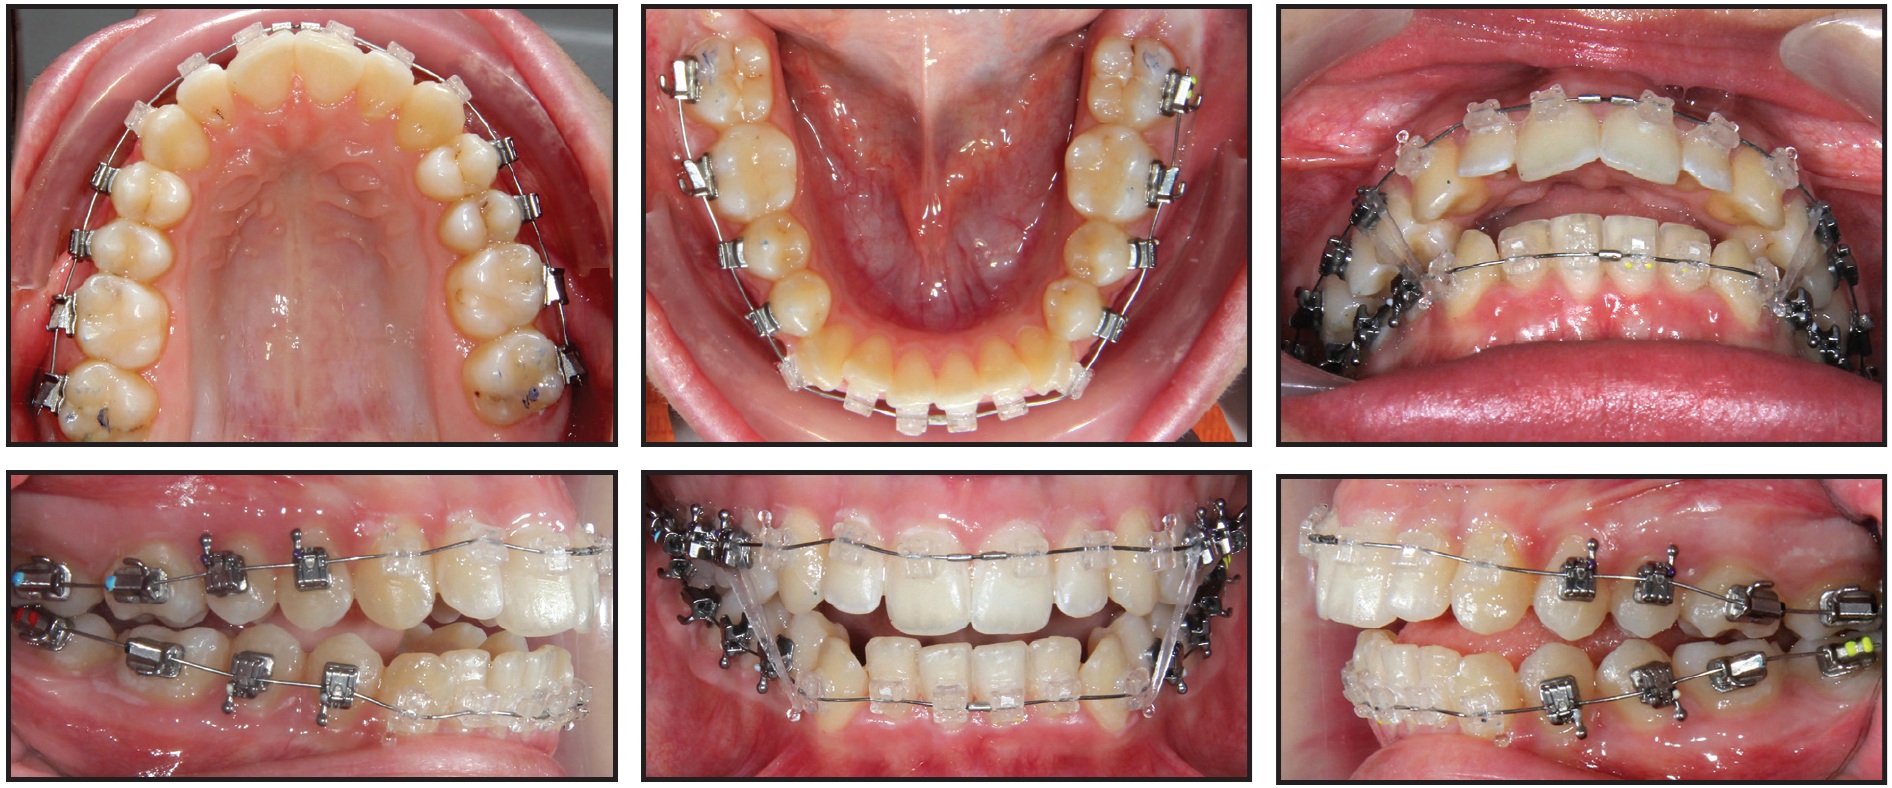

A technique known as the “Active Early” approach comprises progressive case-management strategies that complement SAP bracket positioning for early 3D control. Occlusal guides (bite turbos) and immediate light, short elastics are used from the beginning of treatment to match the lower occlusal plane with the upper. In a patient with deep overbite, this technique helps erupt the lower molars and extrude the upper anterior teeth as it moves them slightly clockwise. Case 1 demonstrates how the smile arc, enamel and gingival displays, and occlusal plane can be positively affected by SAP bracket positioning and the “Active Early” approach (Figs. 1-6).

Fig. 1 Case 1. 17-year-old female patient with disappointing result from previous 3.5 years of orthodontic treatment. (Case courtesy of Dr. Nimet Guiga, Cascais, Portugal.)

Fig. 2 Case 1. Brackets bonded with Smile Arc Protection (SAP) bracket positioning. Progressive case management strategies included inverted upper anterior brackets; posterior occlusal guides (bite turbos); and immediate light, short Class III elastics.

Fig. 3 Case 1. Smile arc developing after eight months of treatment.

Fig. 4 Case 1. Patient after 15 months of treatment, with smile exhibiting all desirable esthetic characteristics.

Fig. 5 Case 1. Comparison of pretreatment (A) and post treatment (B) photos, demonstrating improvements in smile arc, cant of upper occlusal plane, incisor and gingival display, and archform, with proper “white and pink” esthetic proportions.

Fig. 6 Case 1. Comparison of pre-treatment (A) and post-treatment (B) lateral cephalograms, showing slight clockwise rotation of maxillary occlusal plane with upper incisor extrusion in relation to stomion.